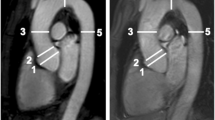

The luminal diameters of the aortic valve (AV) annulus, sinuses of Valsalva, and the sinotubular junction (STJ) were measured in both systole and diastole by a single observer (LMH). In this study, the image reconstruction protocol suggested by Schultz et al. [15] was used. Axial cuts through the aortic root were obtained by aligning the three perpendicular imaging planes (one axial and two longitudinal, respectively, oblique sagittal and oblique coronal; Fig. 1). To identify the true short axis, one imaging plane was aligned parallel to the AV annulus. The alignment with the AV annulus was checked in the other imaging planes. The definition of the AV annulus is controversial. From anatomical and surgical perspective, the valve leaflets are attached within the cylinder of the root in the form of a coronet [5]. According to Anderson et al. [5] proper values of the annular dimension can only be provided when measurements are made at the bottom of the leaflet attachments. Therefore, the level of the aortic valve annulus on CT is defined as the lowest level of insertion of the valve leaflets into the aortic root. The oblique sagittal plane was then modified by defining it in the axial window at the level of leaflet coaptation as the line running through the commissure and along the coaptation line of the left and non-coronary cusps thereby dividing the right coronary sinus into visually equal halves. The oblique coronal plane was defined as the line orthogonal to and crossing the oblique sagittal at the point of central leaflet coaptation. Subsequently, measurements of the root were performed at three levels on the appropriate in plane slices.

The maximal diameter (Dmax) at this level was measured in the in plane images. Perpendicular to this line, a second short axis diameter was measured (Dmin). According to Tops et al. [6] the annulus was defined as oval if the difference between these two measurements was greater than 3 mm. For the sinuses of Valsalva the diameter was measured as a line extending from each of the three commissures to the middle of the opposite coronary cusp. The Dmax and minimal diameter were used for analysis. The STJ was measured at the junction of the sinuses and the tubular portion of the ascending aorta (Fig. 2). The differences between systolic and diastolic dimensions were determined (systolic minus diastolic dimension) and plotted in a histogram to examine the distribution of the variance.

The diameter of the AV annulus, STJ and sinuses of Valsalva was also measured on the oblique coronal view (Fig. 2). The Dmax and Dmin on the double oblique transverse view and the diameter on the coronal view were compared, resembling the comparison between 3D and 2D measurements, respectively.

The aortic annulus or base of the native leaflets was defined as the axial plane just beneath the most caudal attachment of all three aortic leaflets (a1). The largest diameter and the diameter perpendicular to this line were measured on the axial image (a2). On the oblique coronal view, the annulus measurement is shown in a3. The sinus of Valsalva dimensions were measured as the line extending from each commissure to the middle of the opposite coronary cusp (b2). On the oblique coronal view, the sinus of Valsalva measurement is shown in b3. The sinotubular junction was measured at the junction of the sinuses of Valsalva and the tubular portion of the ascending aorta (c1). The largest diameter and the diameter perpendicular to this line were measured on the axial image (c2). On the oblique coronal view, the sinotubular junction measurement is shown in c3